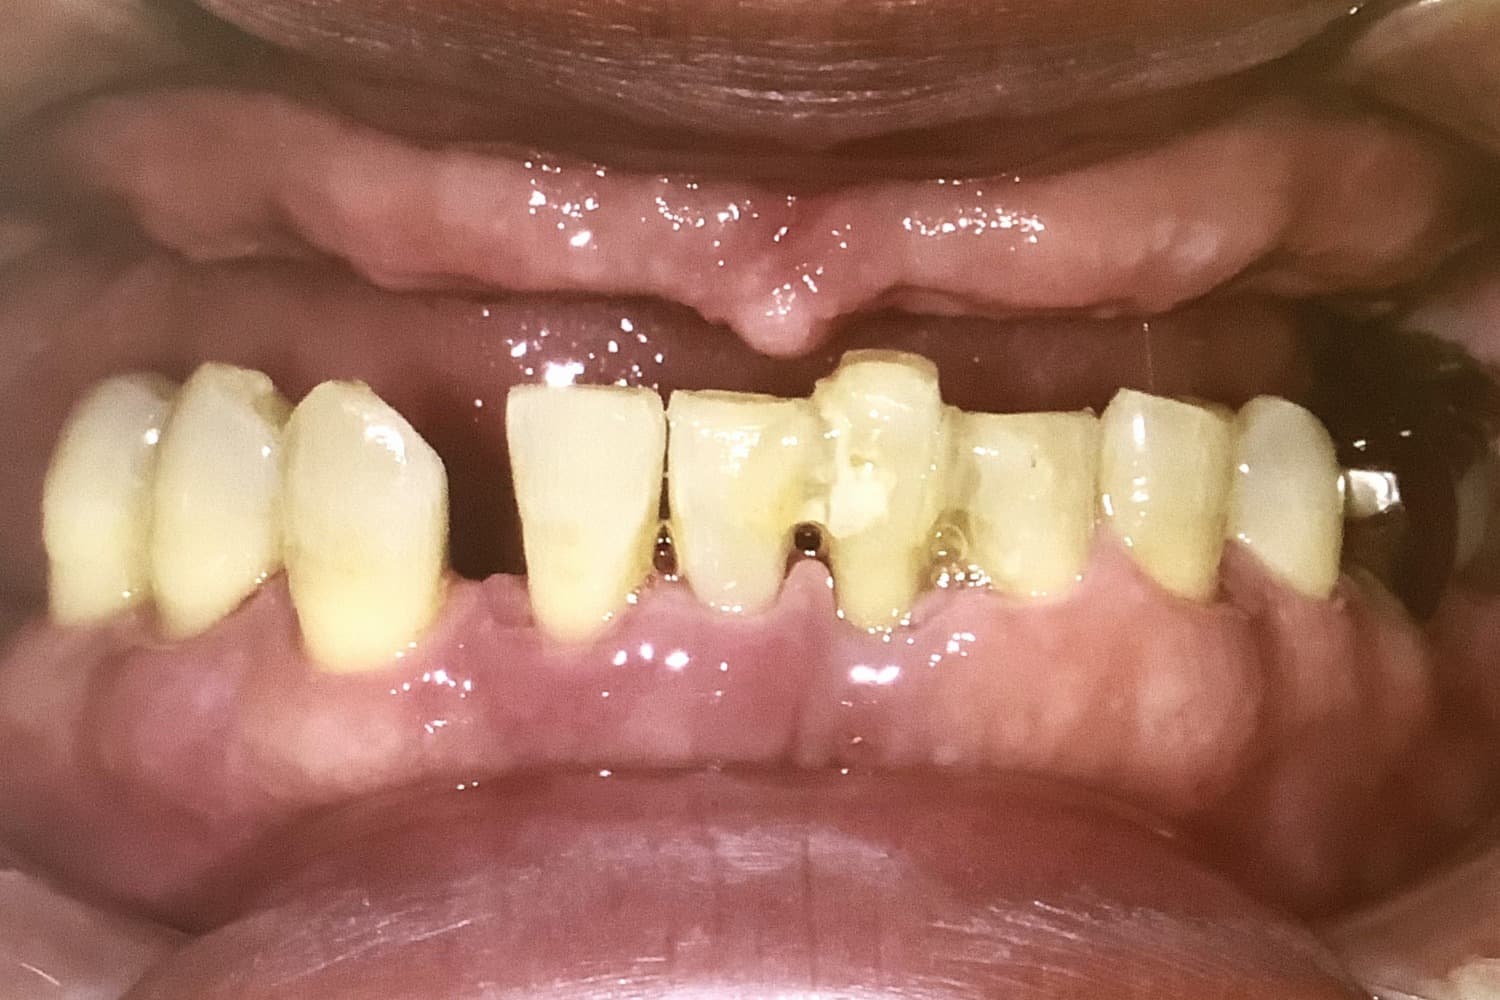

上顎のインプラント治療

Before

上顎に8本インプラントを埋入手術しブリッジ冠を用いて修復した

年齢

50

性別

男性

主訴

上顎の総入れ歯が嫌なのでインプラントにしたい

治療期間

8ヵ月

治療回数

8回

費用

2,860,000円

副作用・リスク

・全身疾患の有無や骨の状態によってインプラント体が骨と生着しない可能性がある ・術後患部が腫れたり痛みが生じたりする可能性がある